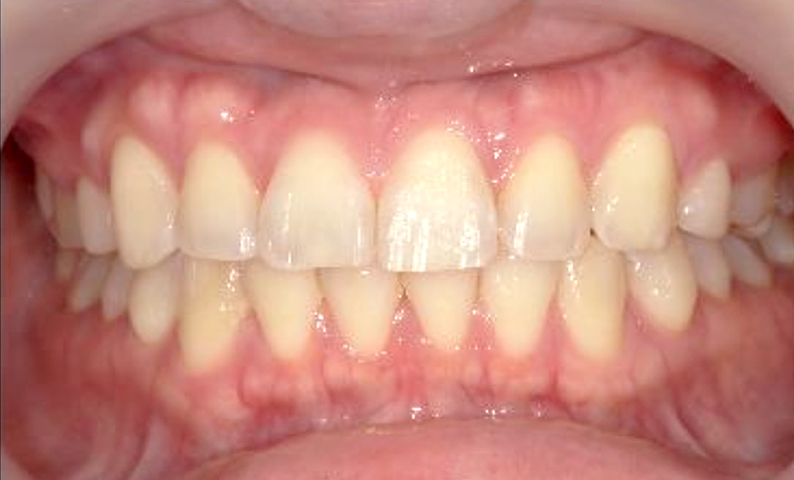

症例_002 前歯「すきっ歯」症例

治療期間:8ヶ月金額:48万円+税20代女性すきっ歯

| Before | After |

|---|---|

|